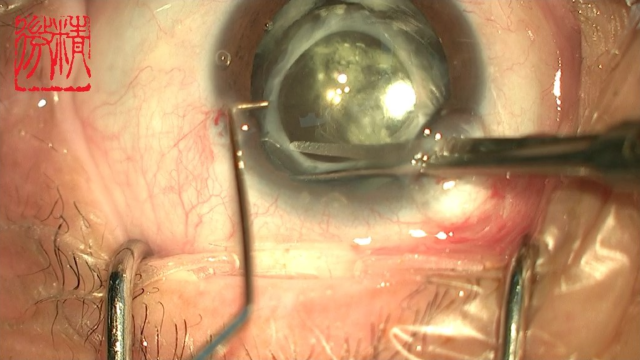

烧伤整形邹普功烧伤科医师

活动背景和目的:我从去年九月份陆续在丁香园写了几十帖有关腋臭微创手术的帖子,受到很多同行老师的关注及跟帖,其中有很多同行老师也在尝试用我的这种方法治疗狐臭,并且收到很好的效果。随着站内外科同行对狐臭微创手术的关注度日渐增高,近期受丁香园邀请,特举办一次关于狐臭微创手术的跟学练活动。这也是本人根据临床工作中的一些手术案例总结的经验,分享给大家一起交流学习。让我们一起做好除臭这件事!各位站友可点击下面狐臭专场链接交流学习(包含本人视频操作教学详解、常见问题讨论和各位站友同行的手术佳作):https://3g.dxy.cn/newh5/view/nodeActivityTopic/270第一期我给大